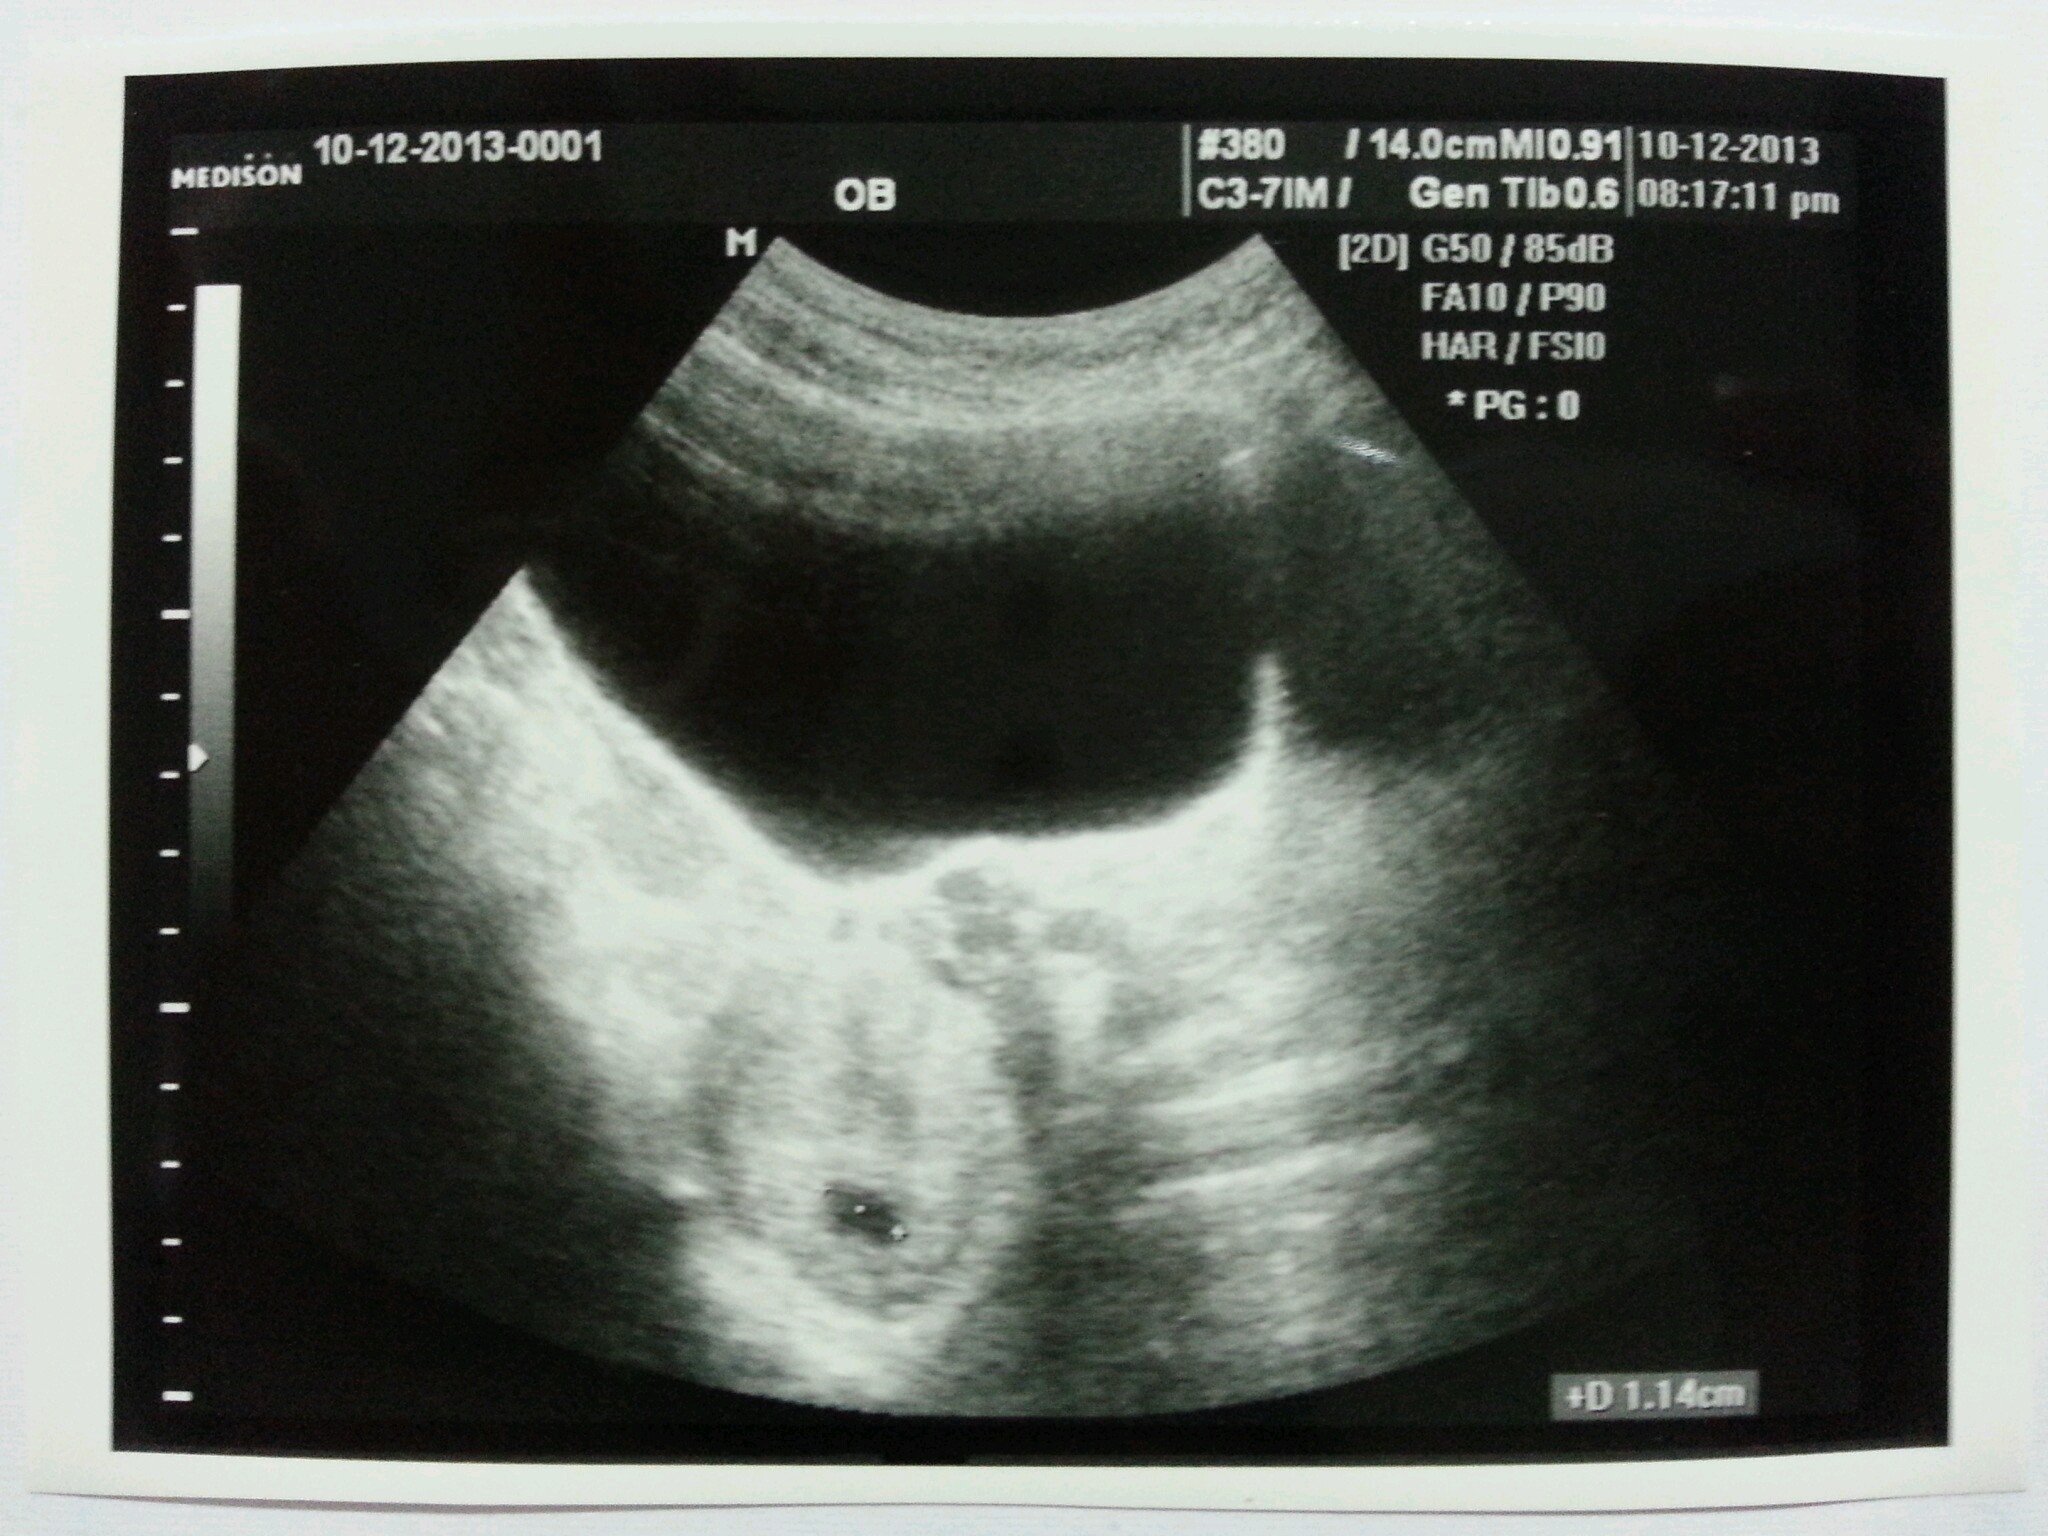

![]() thank God it wasn’t! The doctor showed us a tiny 1.14cm sac that looked tiny and … meaningless. Seriously, I wasn’t that excited at all and I could see that dear hubby wasn’t too thrilled as well. Hahaha. We were obviously wanting to see something bigger, or at least having more shapes.

thank God it wasn’t! The doctor showed us a tiny 1.14cm sac that looked tiny and … meaningless. Seriously, I wasn’t that excited at all and I could see that dear hubby wasn’t too thrilled as well. Hahaha. We were obviously wanting to see something bigger, or at least having more shapes.

The doctor said that everything is fine and the pregnancy is around 6 weeks. I checked online the next day, the estimated due date is on 5th August 2014 which is 3 days after hub’s birthday! When we were engaged, I actually joked that I wouldn’t want to have our kids born on August because hub’s and his sister’s birthday are on August. I think we need to have a more spread out birthdays so we can have celebrations through out the year. Well now, so much for having party all year long.